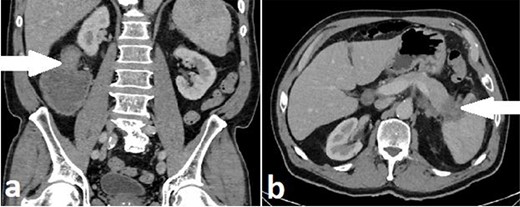

Routine staging for rectal cancer was performed. Magnetic resonance imaging (MRI) of the pelvis revealed an anterior rectal mass 7–8 cm from the anal verge with invasion into the seminal vesicles and at least three lymph nodes suspicious for metastases (cT4aN2). Computed tomography (CT) chest, abdomen and pelvis revealed enlarged nodes along the inferior mesenteric artery chain, but no definite metastatic disease was reported (Fig. 2). A 1.4 cm low attenuation hypo-enhancing mass in the distal pancreas occluding the splenic vein was reported as an incidental finding. Serum carcinoembryonic antigen (CEA) was 1.71ug/L and serum carbohydrate antigen 19-9 (Ca 19-9) was mildly elevated at 78u/ml.

Case A. Axial portal venous phase CT scan demonstrating hypo-enhancing distal pancreatic lesion encasing splenic vessels (a) and sagittal MRI pelvis demonstrating anterior low rectal tumour (b), staged as a cT4aN2Mx rectal adenocarcinoma.